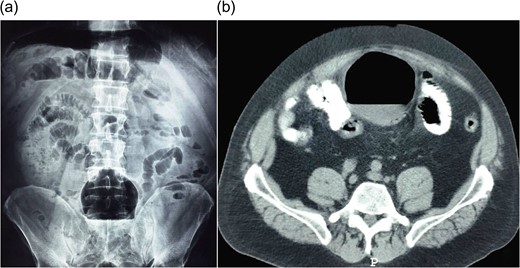

A plain abdominal X-ray presented a solitary, air-filled structure with smooth margins in the lower abdomen, while a chest X-ray revealed the presence of free air in the abdominal cavity (Fig. 1a). An abdominal computed tomography (CT) scan showed a large, 9 × 9.5 cm2, thin-walled, cyst-like lesion with air-fluid level adherent to the sigmoid colon as shown in Fig. 1b.

(a) Abdominal X-ray shows an air-filled structure in the lower abdomen (Balloon-sign). (b) Abdominal CT scan shows an air-filled cavity associated with the colon.

Abdominal X-ray and CT scan are the investigations of choice for diagnosing GCD. A large, smoothly marginated, air-filled cyst (‘Balloon-sign’) with or without air-fluid level is revealed on the abdominal X-ray [5]. An abdominal CT scan shows an air-filled cavity associated with the colon. Barium enema can demonstrate the communication with the bowel lumen in 60–70% of the cases. However, perforation may occur as a complication [6].